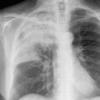

Case 3 RM & UL pneum PA

Date: 07/04/2004

Views: 5509